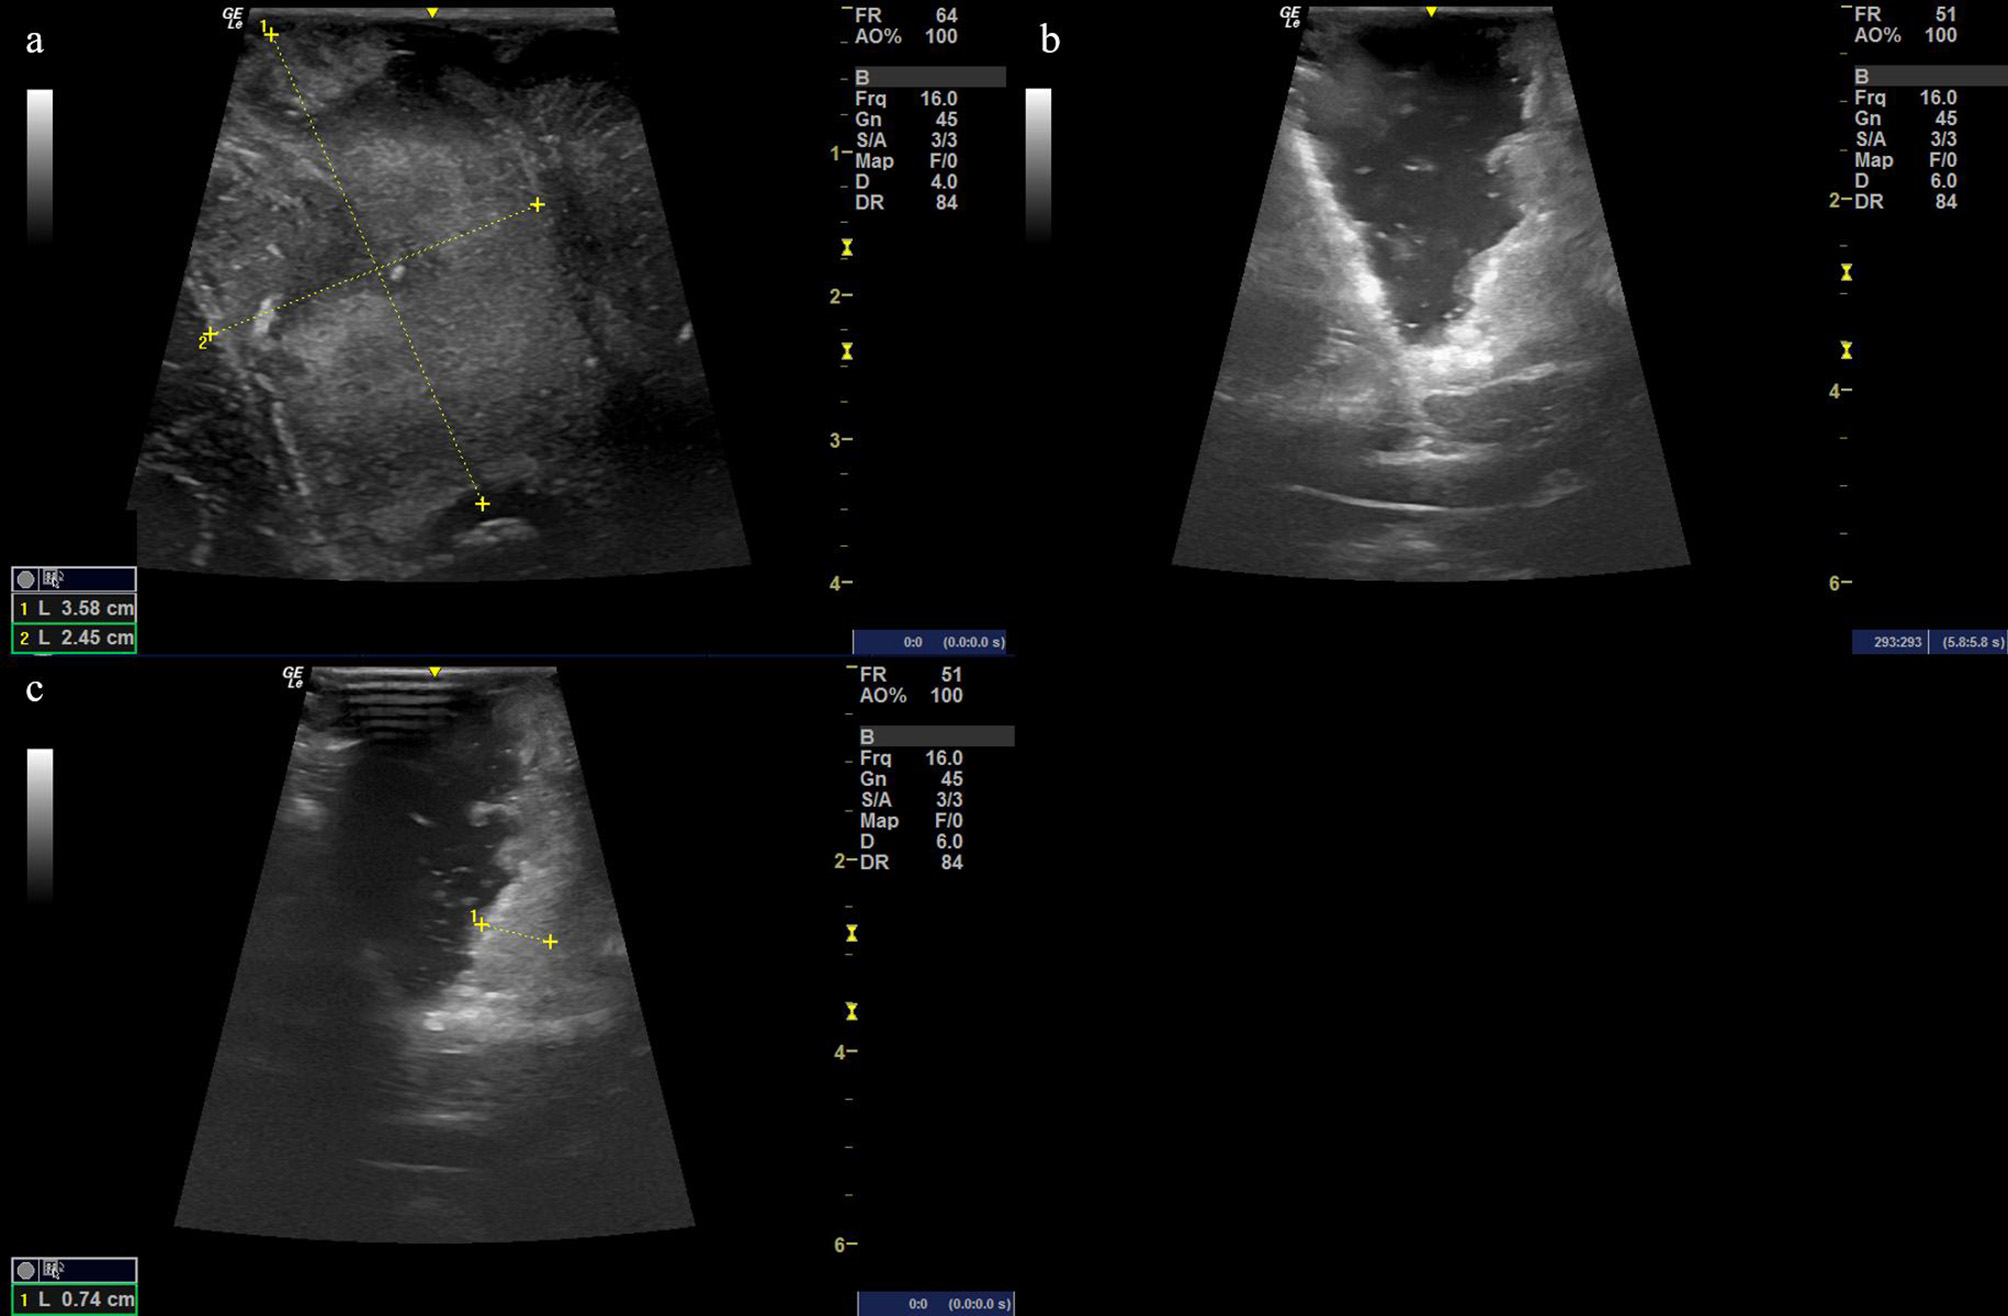

Figure 4

(a) Ultrasound image before cutting the dural matter displaying the occupying lesion of hyperechoic signal with the size of the possible solid tumor being 3.58 cm × 2.45 cm. (b, c) The resection procedure of a residual tumor guided by the intraoperative ultrasound scan, showing the extent of the resection area.